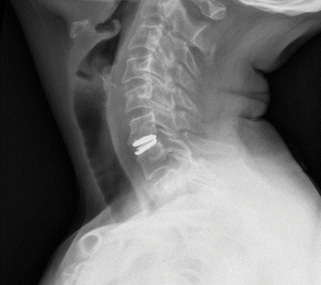

Patient is a healthy, active 58 year-old female, though with advanced degenerative spondylosis at a low cervical level. The patient had favorable anatomy with a long neck and low shoulders to facilitate intraoperative visualization. Fusion was appropriate in this case, but intraoperatively, though we were prepared for this possiblity, the disk space was well-preserved and mobilized without major modification of the endplates. The postoperative flexion and extension radiographs showed movement at the spinous processes of C6/7 and good function of the prodisc C Vivo prosthesis. The adjacent C5/6 level also shows degenerative spondylosis. By optimizing the mobility of the C6/7 level I anticipate the patient will have an improved trajectory for her cervical spine function throughout her life.